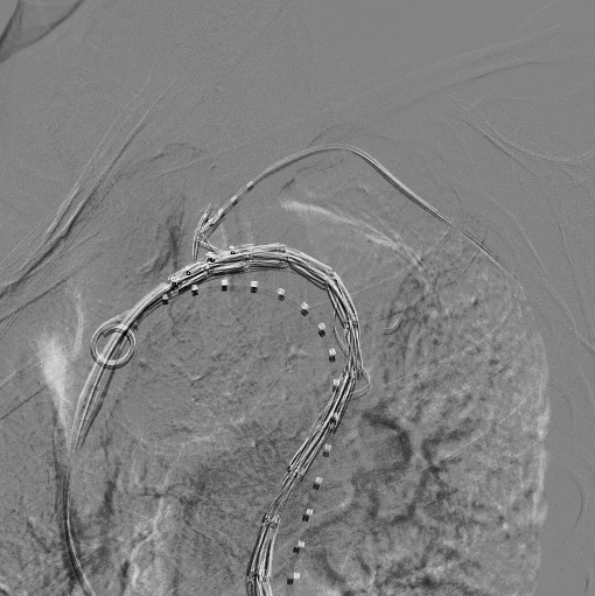

上推Hercules®直管型支架

对降主直段进行造影,经右侧股动脉导丝上推Hercules®直管型支架至胸降主动脉,定位并释放支架,隔绝胸降主动脉病变;

治疗车怎么推「弓部重建直通车」鄂尔多斯市中心医院康巴什部介入科运用Castor®分支型支架联合预开窗技术治疗Stanford B型胸主动夹层_https://www.jmylbn.com_新闻资讯_第10张

上推Hercules®支架